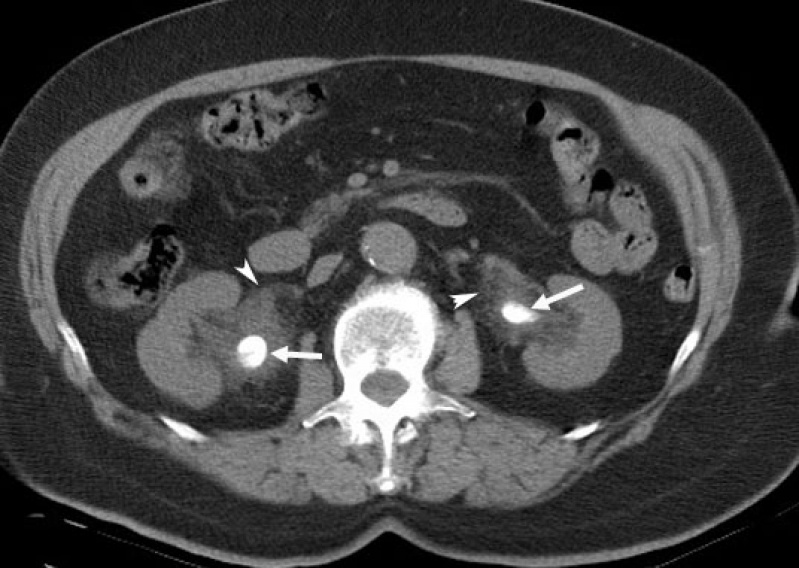

Com um exame de tomografia é possível captar imagens em tons de cinza de determinadas partes do corpo ou de algum órgão do paciente. A preparação para realizar o exame de tomografia é simples e consta apenas de cuidados anti-alérgicos.